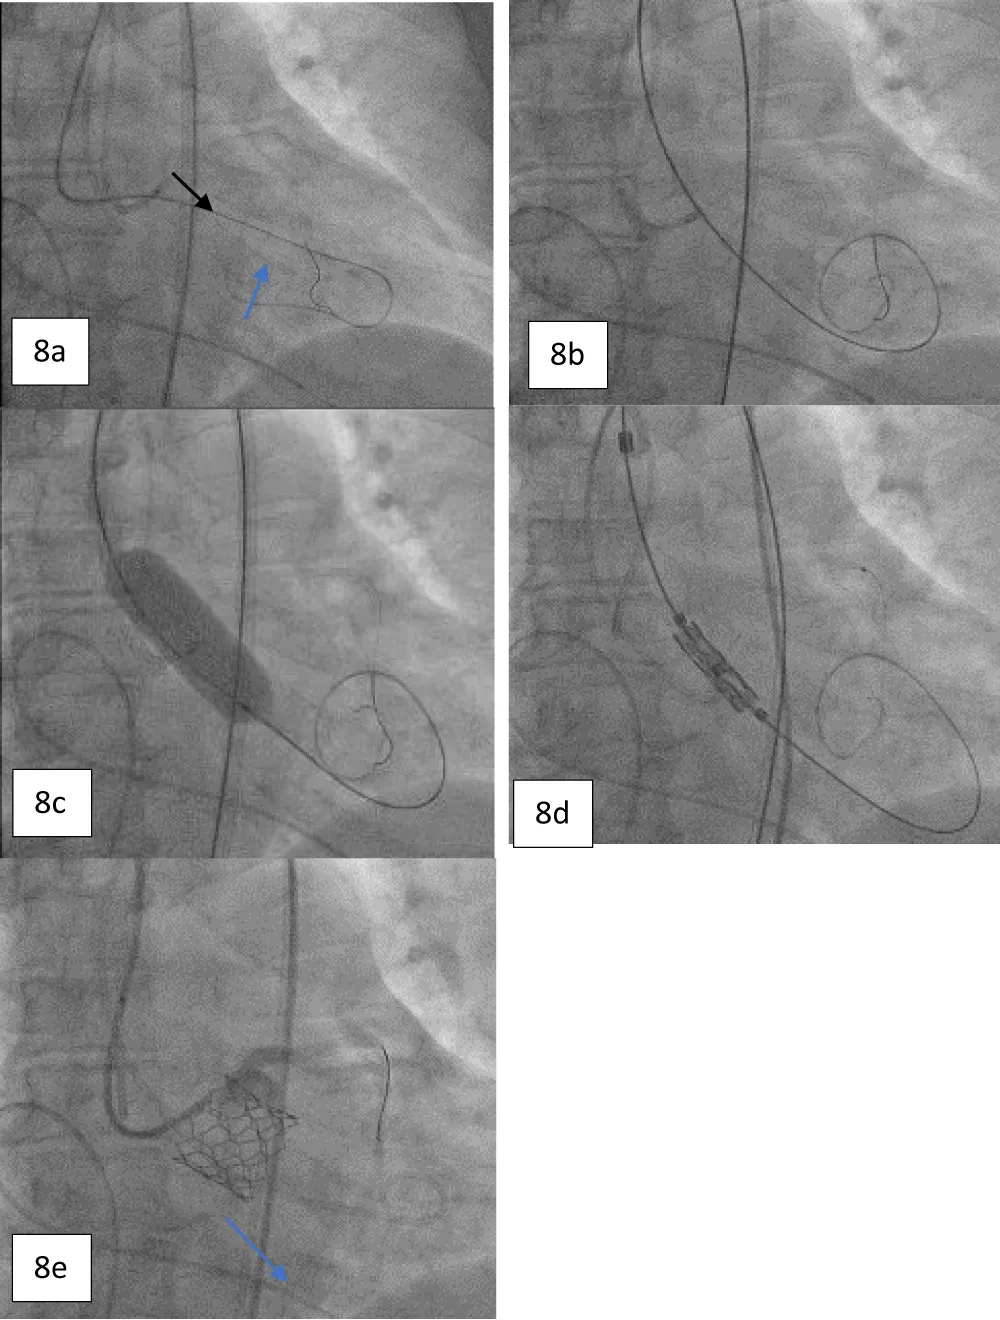

On the day of the procedure, after the patient registration process, the patient was taken to the cardiac catheterization laboratory, where she was placed under conscious sedation. The procedure was started by inserting a pigtail catheter through the left femoral artery and placing it at the non-coronary cusp of the aortic root to measure the AV hemodynamics. A temporary pacing lead wire was inserted through the left femoral vein and placed in the right ventricle. Thereafter, the LMCA was cannulated to provide coronary protection after introducing a coronary guiding catheter through the right radial artery with a straight-tip 0.014” Runthrough® coronary guidewire (Terumo Corporation, Tokyo, Japan) through a guide extension catheter (Guidezilla II; Boston Scientific Corporation, Marlborough, Massachusetts, USA) (Figure 8a-8e). The native AV was crossed using an AL-1 guiding catheter and a straight-tip guidewire (GLIDEWIRE® Standard, Terumo Corporation, Tokyo, Japan) was inserted. Thereafter, the AL-1 catheter was exchanged with a pigtail catheter and an extra-stiff supportive guidewire (Safari™; Boston Scientific Corporation, Marlborough, Massachusetts, USA) was placed in the LV apex. The 14-Fr Python Introducer sheath was advanced through the right femoral artery for the delivery of the selected 21.5 mm BE Myval valve. Pre-dilatation was performed using a 20 × 40 mm Mammoth™ over-the-wire balloon (Meril Life Sciences Pvt Ltd., Vapi, India) followed by the deployment of a 21.5 mm BE Myval THV under rapid pacing. Post-dilatation was performed by adding 1 cc extra volume to the 21.5 mm balloon of the Navigator™ THV delivery system (Meril Life Sciences Pvt Ltd., Vapi, India) that carried the crimped Myval THV. The postprocedural aortogram showed normal coronary flow and patent LMCA, while the postprocedural 2-D echocardiograph showed the mean and peak AV gradients of 10 mmHg and 18 mmHg, indicating stable hemodynamics without any aortic regurgitation or residual pressure gradient across the AV (Figure 9). Hence, the coronary guiding catheter was retracted. Both the femoral and the trans-radial access sites were closed with Perclose Proglide® suture-mediated foreclosure (Abbott Cardiovascular, Santa Clara, California, USA).

Figure 8: a. Angiogram showing the protection of the LMCA using a guide extension catheter and a supportive coronary guidewire (black arrow) with cannulation; crossing the diseased aortic valve using an AL-1 guiding catheter and a standard straight-tip wire (blue arrow). b. Guidewire exchange using a Safari stiff wire advanced across the valve. c. Pre-dilatation performed with a 20 x 40 mm Mammoth over-the-wire balloon. d. Positioning of 21.5 mm balloon-expandable Myval THV. e. Angiogram obtained post deployment showing the patent LMCA (blue arrow).